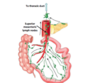

Made up of a number of ducts which transport bile

- Right + left hepatic duct = Common hepatic duct

- Common hepatic duct + common bile duct = Common bile duct

How does drainage from the biliary system occur

- Bile duct descends posteriorly to the 1st part of doudenum

- Then travels into a groove on the posterior aspect of the pancreas

- Bile duct joins with the main prancreatic duct to form the ampulla of vater- wider duct

- both drain Into the major doudenal papilla in 2nd part of doudenum

there are 2 papillas in the 2nd part of the doudenum what are they and what do they drain

- Major papilla - drains ampulla of vater

- Minor papilla - drains accessory pancreatic duct

What are the sphincters related to secretion into the doudenum

- Dile duct sphincter

- Sphincter of oddi

- pancreatic sphincter